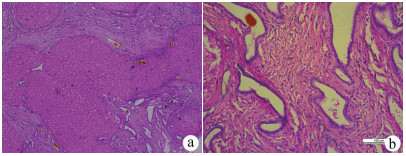

肝癌肉瘤合并肝细胞癌1例报告

李日, 郭怀斌, 梁泽, 李娜, 温军业, 张万星

2021, 37(9): 2180-2182. DOI: 10.3969/j.issn.1001-5256.2021.09.034

摘要(1271) HTML (266) PDF (4255KB)(64)

摘要: